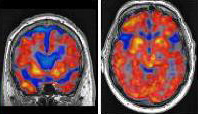

Imaging Neuroinflammation in Neurodegenerative Disorders

Neuroinflammation may be a key mediator of neuronal dysfunction and cell loss in neurodenegerative disorders. Using the hybrid PET/MRI scanner at Lawson Health Research Institute and a PET ligand that can bind to activated immune cells in the brain, in collaboration with scientists Keith St. Lawrence, Udunna Anazodo, Michael Kovacs and Justin Hicks we are examining whether patients with Frontotemporal Dementia and related disorders exhibit greater inflammation in their brains that healthy aged matched controls.